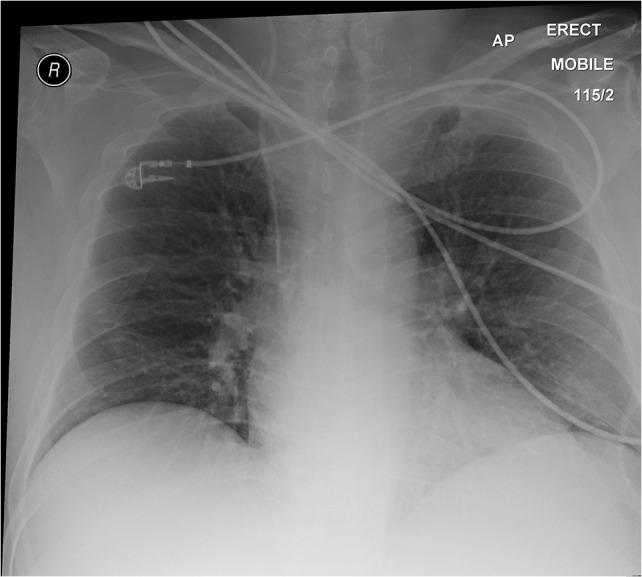

Meckel's diverticulum is the most common congenital abnormality of the small intestine that results from incomplete closure of the vitelline (omphalo-mesenteric) duct. This true diverticulum, ~2 ft from the ileocecal valve commonly found on the anti-mesenteric border of the ileum, is benign and majority asymptomatic. Diagnosis challenges arise when it became inflamed or presented in following ways, for example, haemorrhage (caused by ectopic pepsin-and hydrochloric acid-secreting gastric mucosa), intestinal obstruction (secondary to intussusception or volvulus) or the presence of diverticulum in the hernia sac (Littre's hernia). We report a case of a 59-year-old male who was admitted under the surgical service at Blackpool Victoria Hospital with suspected appendicitis that turned out to be a Meckel's diverticulitis, a rare presentation of an acute abdomen. We discuss the issues involved in his investigation and management as well as perform a literature review comparing different surgical approaches.

梅克尔憩室是小肠最常见的先天性异常,由卵黄管(脐肠系膜管)未完全闭合引起。这个真性憩室通常位于回肠对系膜缘,距离回盲瓣约2英尺,是良性的,大多数无症状。当它发炎或以以下方式出现时,诊断就会面临挑战,例如出血(由异位分泌胃蛋白酶和盐酸的胃黏膜引起)、肠梗阻(继发于肠套叠或肠扭转)或疝囊内存在憩室(里特疝)。我们报告一例59岁男性患者,他因疑似阑尾炎入住布莱克浦维多利亚医院外科,结果诊断为梅克尔憩室炎,这是一种罕见的急腹症表现。我们讨论了其检查和治疗中涉及的问题,并对不同手术方法进行了文献综述比较。